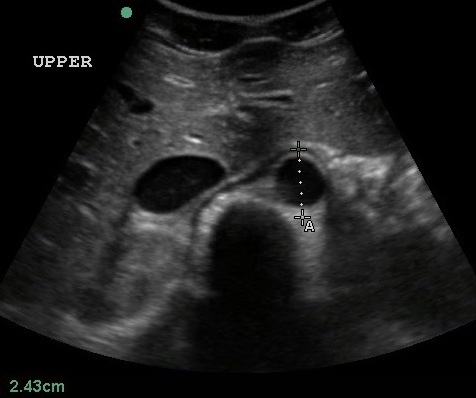

- At least 3 transverse views, labeled, “proximal”, “mid”, “distal” with calipers should be recorded. One view should show the maximal aortic diameter.

- Proximal measurements should be obtained around the celiac trunk or liver tip.

- Figure 3. Transverse view of the proximal aorta